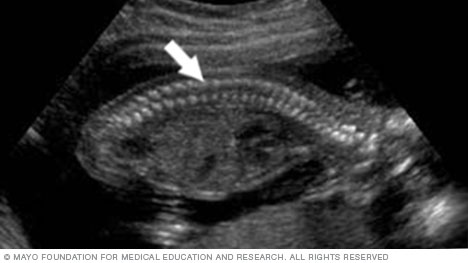

Below is an image of the base of the brain, called the cerebellum. This type of image usually is taken during an ultrasound done between 18 and 22 weeks of pregnancy.

The cerebellum is the part of the brain that controls muscle coordination and balance. Checking its shape on an ultrasound can help the health care team find neural tube defects. The neural tube forms in the first few weeks of pregnancy. The top of the tube becomes the brain. The rest of it becomes the spinal cord. Problems in neural tube development may lead to conditions such as spina bifida, in which part of the neural tube doesn't develop or close correctly. This can lead to problems in the spinal cord and in the bones of the spine.